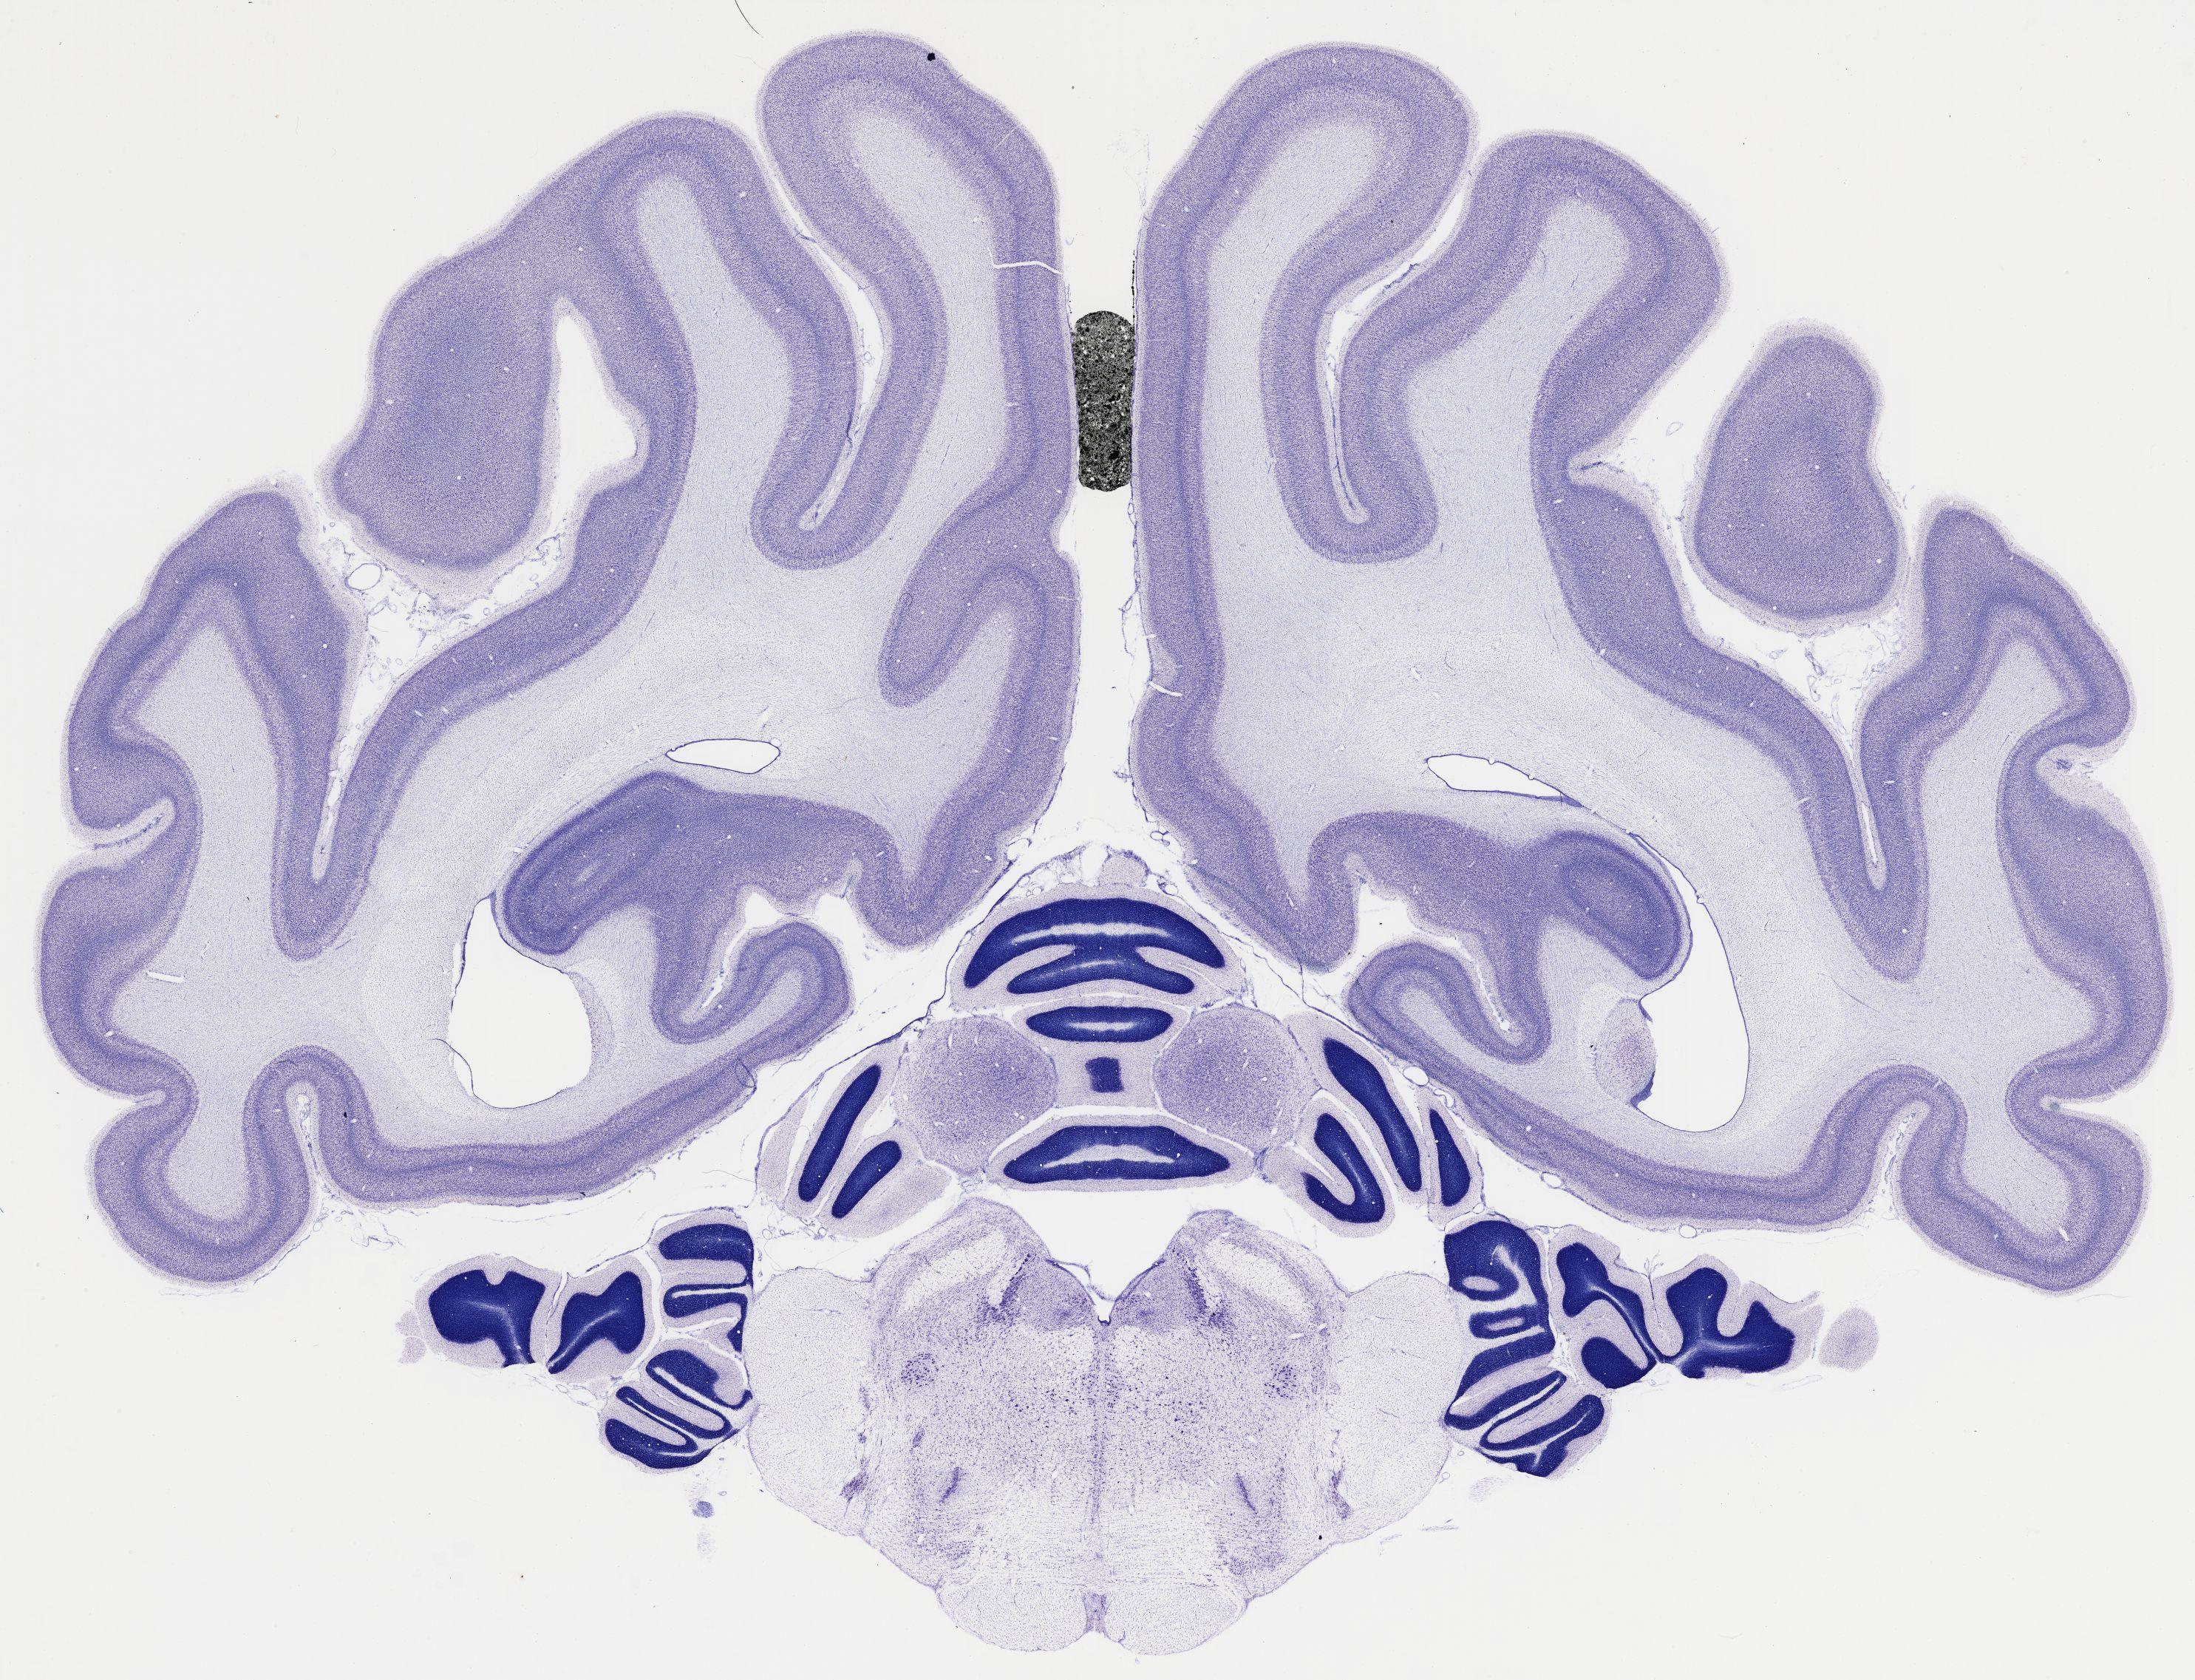

Datasets -> Chlorocebus Aethiops -> Nissl, coronal, histo, Whole-Brain, adult

[ Metadata ]   ·   Source: NeuroScience Associates

thumbnail

523